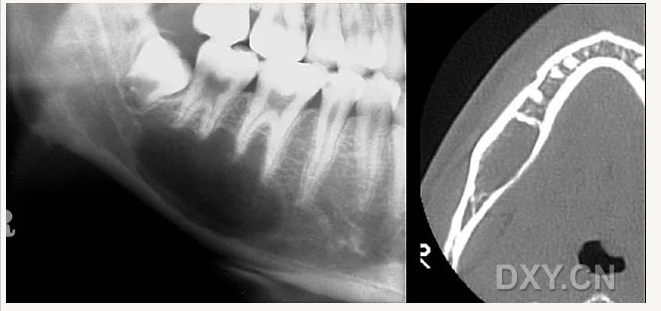

頜骨骨折

大理石骨?。ㄏ骂M骨有明顯的骨化影像,恒牙埋伏)